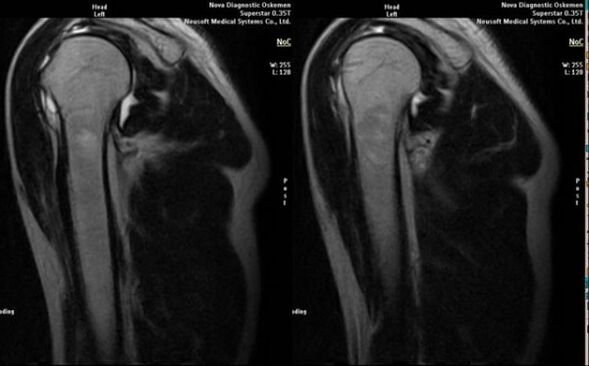

- risonanza magnetica e tomografia computerizzata;

I segni che indicano lo sviluppo dell'artrosi includono direttamente la comparsa di un significativo restringimento dello spazio articolare, la sclerosi delle strutture sottocartilaginee, l'assottigliamento dello strato condrocitario stesso, la comparsa di osteofiti e la deposizione di cristalli di sale nel fluido intrarticolare.